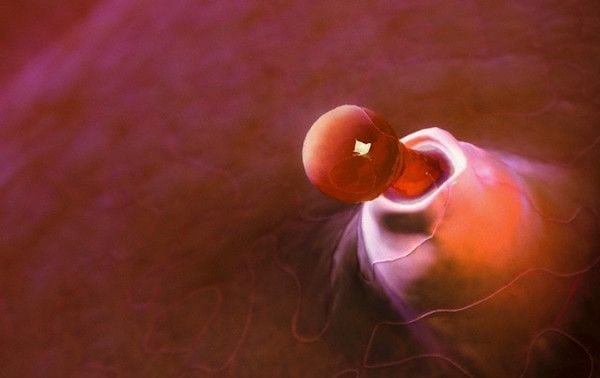

The vertebral disc is a circular and flattened structure similar to a hamburger or giant lentil, placed between the anterior and most solid part of the vertebrae: the vertebral bodies; which acts as a shock absorber and allows anteroposterior flexion-extension movements, also lateral and a certain degree of torsion.

It is composed of a fibrous peripheral part and a gelatinous central part. The external one gives consistency and the internal elasticity. Being two different parts, they act in a coordinated way, allowing the flexibility of the spine.

When excessive or sudden efforts, alterations in feeding or hydration, or even trauma, act on them, these discs can become dislodged, damaged and can, therefore, give rise to pathology and pain at that level, whether localized or irradiated.